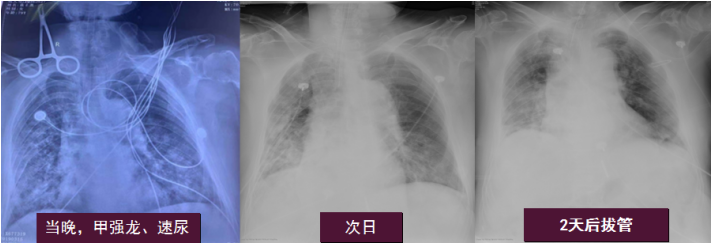

在常规气管镜、适当镇静情况下,通过局部麻醉缓慢完成TBLB操作。患者肺泡灌洗液脱落细胞阴性,肺泡灌洗液未查到癌细胞。最终经活检证实为黏液腺癌。(5)冷冻肺活检 & TBLB:冷冻肺活检也是近年来开展比较多的一项技术,尤其在弥漫性间质性肺疾病的诊断中发挥了重要作用。此项技术不仅可以在手术室完成,也可以在床旁完成。病例:男性,67岁,鼻塞伴双上肢肌肉酸痛2天,呼吸困难1天。血常规:WBC 14.48×109/L,NEU% 87.5%,RBC 5.34×1012/L,Hb 117 g/L,PLT 99×109/L;血气分析提示Ⅰ型呼吸衰竭。入院即刻床旁气管镜检查。BALF和保护毛刷培养均阴性,病原微生物NGS结果阴性,TBLB病理提示慢性炎症。治疗前后胸部CT如图4所示。呼吸内镜下常用的介入技术包括:气管支架植入/球囊扩张等机械性迅速改善气道通气/畅的能力,清理气道内异物、分泌物、止血技术,经口/鼻气管镜引导下气管插管,电切刀/电凝/氩等离子体(APC)/激光等热消融技术,冷冻/药物注射等。(1)治疗性肺泡灌洗:患者女性,79岁,溺水10小时,气管插管下于2019年3月15日7:30 pm转入RICU。入院后迅速进行肺泡灌洗,清理肺内恶性分泌物,患者得到及时有效的救治。患者胸片变化如图5所示。(2)威胁生命大咯血救治:吸引清除气管内凝血块,最大限度地保障气道通畅和有效的气体交换;对于威胁生命的大咯血,支气管镜可在其他特定手段干预之前,迅速提供有价值的治疗性止血措施;气管镜处理时机:84%的介入肺脏病医生会在咯血24 h内行气管镜检查。对于大咯血,有两种方式治疗:局部治疗(冰盐水灌注, 肾上腺素盐水, 血管加压素, 凝血酶纤维蛋白原复合物, 氨甲环酸, 氧化再生纤维素医用蛋白凝胶等)和气管腔内治疗[Fogarty球囊封堵器, 硅胶塞, 热消融技术(激光、APC、冷冻),双腔气管插管]。可以在短期内尽可能地控制出血,为后续治疗争取时间。(3)快速解除气道梗阻—气管支架植入/球囊扩张等:气管内肿瘤或气管食管瘘患者引发严重呼吸困难,气管支架是重要的解决方法之一。对于急症患者,支架置入的推广和培训相对比较容易。临床中还能会通过球囊扩张等方法来解决一部分气道的问题。(4)气管镜引导下经皮扩张气道造口术(PDT):1985年Ciaglia等报道,PDT目前已经应用已经越来越广。与外科相比,PDT减少了出血,缩短了手术操作时间,降低了医疗费用,减少了切口感染机会。此项技术的并发症发生率在5%左右,但仍有致命性并发症的发生风险。一项研究分析了70例与PDT相关的死亡病例,结果发现,PDT相关死亡率为0.17%,致死性并发症主要是血管损伤和气道相关并发症。因此建议:认真筛选患者,由气管镜引导下行PDT。(5)取气管内异物:气管内取异物相对简单,但对于手术耐受性差的患者仍然存在一定风险,注意选择适宜的器械和技术取异物,做好并发症的应对。(1)呼吸内镜介入技术的规范化培训和推广:保证质量以及使结果同质化。例如:肺泡灌洗如何提高阳性率?如何预防和避免并发症?是否真正把握了合适的适应证和禁忌证——哪些患者需要做,哪些患者不需要做?是否真正明晰了操作的目的和价值?如何规范化放置急症气管支架?如何处理出血等并发症?如何保证和监管各种介入操作技术的质量?一项针对麻醉医师的全国性横断面研究纳入了2016年10月27日至2016年11月27日期间1935份关于困难气道处理的问卷回复,当出现意外困难气道时,63%的10年以下麻醉医师和65%的10年以上麻醉医师会在尝试1~2次后寻求帮助(P=0.000)。超过70%的受访者表示他们更喜欢套管环甲膜切开术来处理紧急气道;受访麻醉师在困难气道评估方面存在培训缺口,培训和使用FONA应急技能,促进国内外气道管理指南的使用;应对年轻医生进行更多的气道管理理论和技能培训,以提高他们的气道管理技能。以色列一项ICU内气道管理问卷调查涉及20个ICU,应答率为70%(20个ICU中有14个),其中71%的ICU采用ASA算法评估困难气道,气管镜下插管在以下两种情况使用频率明显高于其他方法:78%的困难气道和64%的颈椎损伤(P<0.0001);只有43%的单位报告召开了质量保证会议。69%的单位负责人对他们的气道管理策略感到满意。(2)创新与发展:需要是发展的动力,实践是发展的基础,创新是发展的源泉。①器械的创新:需要更为清晰价廉的不同型号的床旁内镜的研发,包括一次性内镜;在临床发现问题并反馈给技术人员,重视医工结合,在临床中寻找新的切点,有更多呼吸介入相关产品的发明和转化。②技术的创新:例如经皮气切技术的不断发展,在新技术的辅助下,使可视化程度不断增加,进一步提高技术的成功率和安全性。(3)呼吸重症团队人才缺口:注重人才建设,需要建立强大的医师队伍、治疗师队伍、护理队伍、护工队伍等。呼吸内镜介入技术与呼吸危重症医学密不可分,呼吸内镜介入技术是呼吸危重症医学发展中不可或缺的关键性技术之一,呼吸危重症医学亦是呼吸内镜介入开展和创新的最后一道安全防线。临床常用介入性诊断和治疗技术包括TBNA、TBLB、冷冻肺活检、肺泡灌洗、支架置入、冷热消融等技术,它们在呼吸危重症患者的救治中有重要的应用价值。当下仍然需要加强呼吸内镜介入技术规范化培训以及专科化呼吸危重症人才队伍的建设。[1] De Jong A, Myatra SN, Roca O, et al. How to improve intubation in the intensive care unit. Update on knowledge and devices[J]. Intensive Care Med, 2022, 48(10):1287-1298. [2] Alhomary M, Ramadan E, Curran E, et al. Videolaryngoscopy vs. fibreoptic bronchoscopy for awake tracheal intubation: a systematic review and meta-analysis[J]. Anaesthesia, 2018, 73(9):1151-1161. [3] Revel MP, Fournier LS, Hennebicque AS, et al. Can CT Replace Bronchoscopy in the Detection of the Site and Cause of Bleeding in Patients with Large or Massive Hemoptysis?[J]. AJR Am J Roentgenol, 2002, 179:1217-1224. [4] Torbiarczyk JM, Sobczak PA, Torbiarczyk KK, et al. Is bronchoscopy always justified in diagnosis of haemoptysis?[J]. Adv Respir Med, 2018, 86:13-16.[5] Hsiao EI, Kirsch CM, Kagawa FT, et al. Utility of Fiberoptic Bronchoscopy Before Bronchial Artery Embolization for Massive Hemoptysis[J]. AJR Am J Roentgenol, 2001, 177:861-867.[6] Charya AV, Holden VK, Pickering EM. Management of life-threatening hemoptysis in the ICU[J]. J Thorac Dis, 2021, 13(8):5139-5158.[7] Haponik EF, Chin R. Hemoptysis: Clinicians’ Perspectives[J]. Chest, 1990, 97:469-475.[8] Ma G, Yang R, Gu B, et al. Tracheal stent placement provides opportunity for subsequent anti-cancer therapy for cancer patients with malignant respiratory complications[J]. Ann Palliat Med, 2021, 10(2):1042-1049.[9] Ciaglia P, Firsching R, Syniec C. Elective percutaneous dilational tracheostomy[J]. Chest, 1985, 87(6):715-719.[10] Ghattas C, Alsunaid S, Pickering EM, et al. State of the art: percutaneous tracheostomy in the intensive care unit[J]. J Thorac Dis, 2021, 13(8):5261-5276.[11] Abbott F, Ortega M, Bravo S, et al. Can we improve teaching and learning of percutaneous dilatational tracheostomy's bronchoscopic guidance?[J]. SAGE Open Med, 2021, ;9:20503121211002321. [12] Bajaj D, Sachdeva A, Deepak D. Foreign body aspiration[J]. J Thorac Dis, 2021, 13(8):5159-5175.[13] Ayats-Vidal R, Vásquez-Pérez A, Gallego-Díaz M, et al. Successful removal of distal persistent foreign body airway with CO2 cryotherapy in a child[J]. Respir Med Case Rep, 2022, 36:101594. [14] Bajaj D, Sachdeva A, Deepak D. Foreign body aspiration[J]. J Thorac Dis, 2021, 13(8):5159-5175. [15] Liu HH, Wang Y, Zhong M, et al. Managing the difficult airway: A survey of doctors with different seniority in China[J]. Medicine (Baltimore), 2021, 100(38):e27181.[16] Haviv Y, Ezri T, Boaz M, et al. Airway management practices in adult intensive care units in Israel: a national survey[J]. J Clin Monit Comput, 2012, 26(6):415-421.